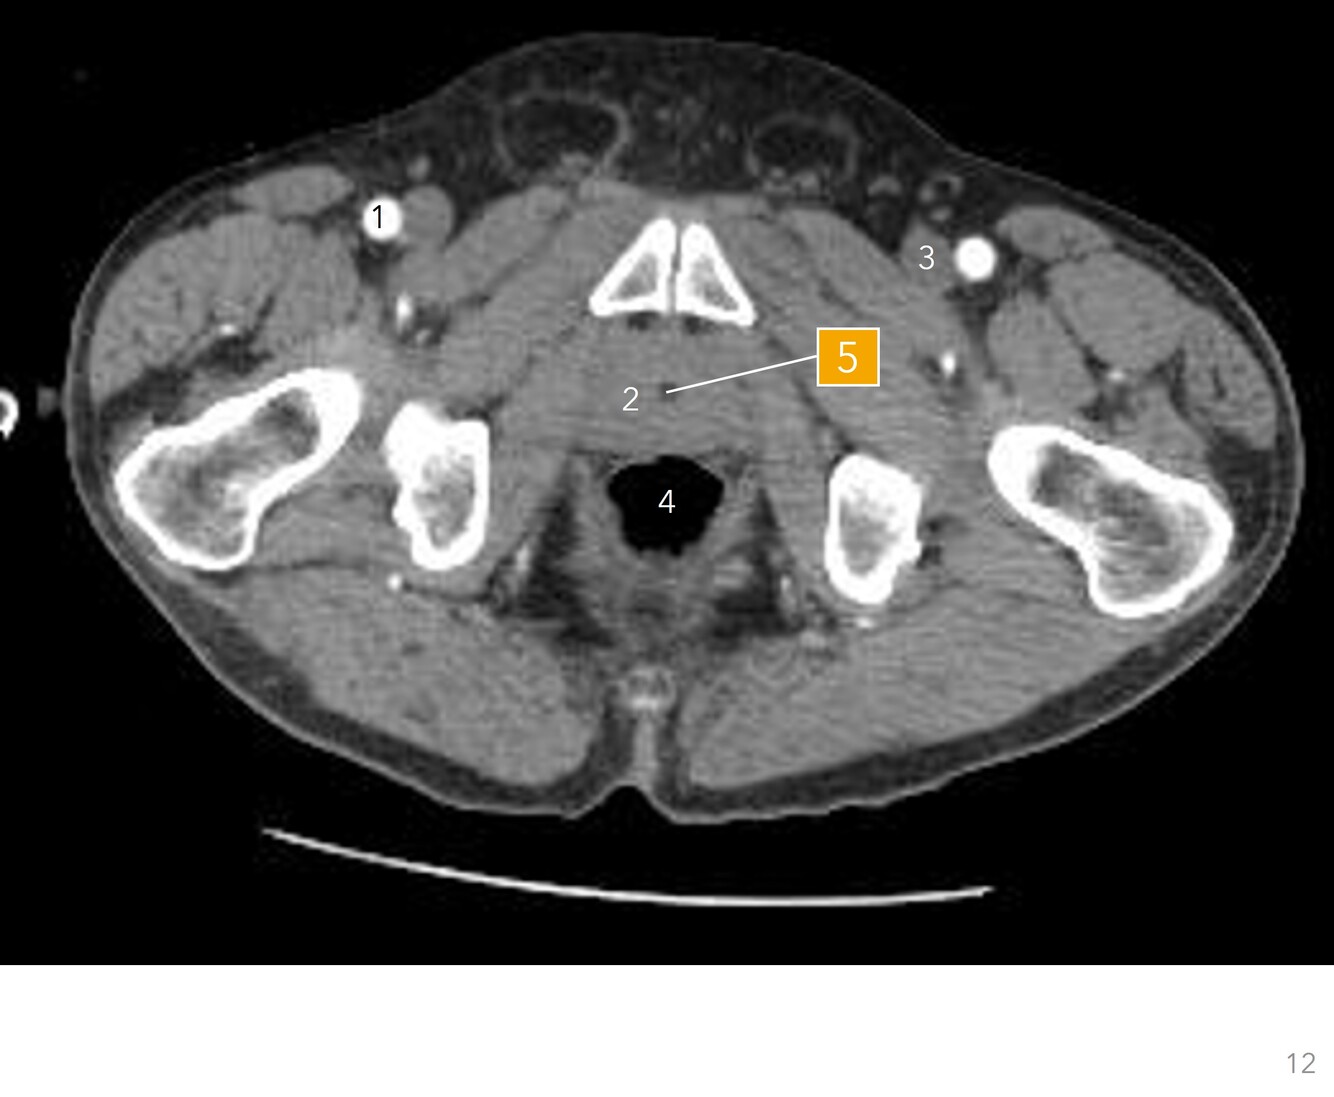

Q

Label 1-5

A

1. Rt femoral artery

2. Prostate gland

3. Lt femoral vein

4. Rectum

5. Prostatic urethra